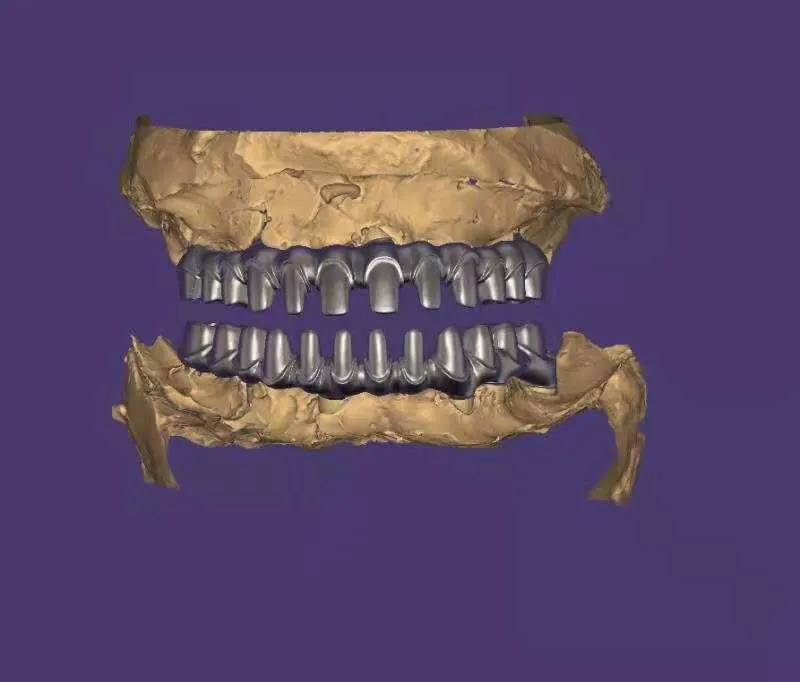

典型的負(fù)重,All-On-4。

這就是傳說中的當(dāng)天戴牙當(dāng)天吃飯,網(wǎng)上到處宣傳的就是這種種植方法。但是不是每一個(gè)人都能做這個(gè),All-on-4一般需要預(yù)約,醫(yī)生種植完畢,技師馬上開始取模做牙,大概5小時(shí)左右就可以戴上臨時(shí)牙回家吃飯了,休息一兩天,正常吃飯是沒問題的。